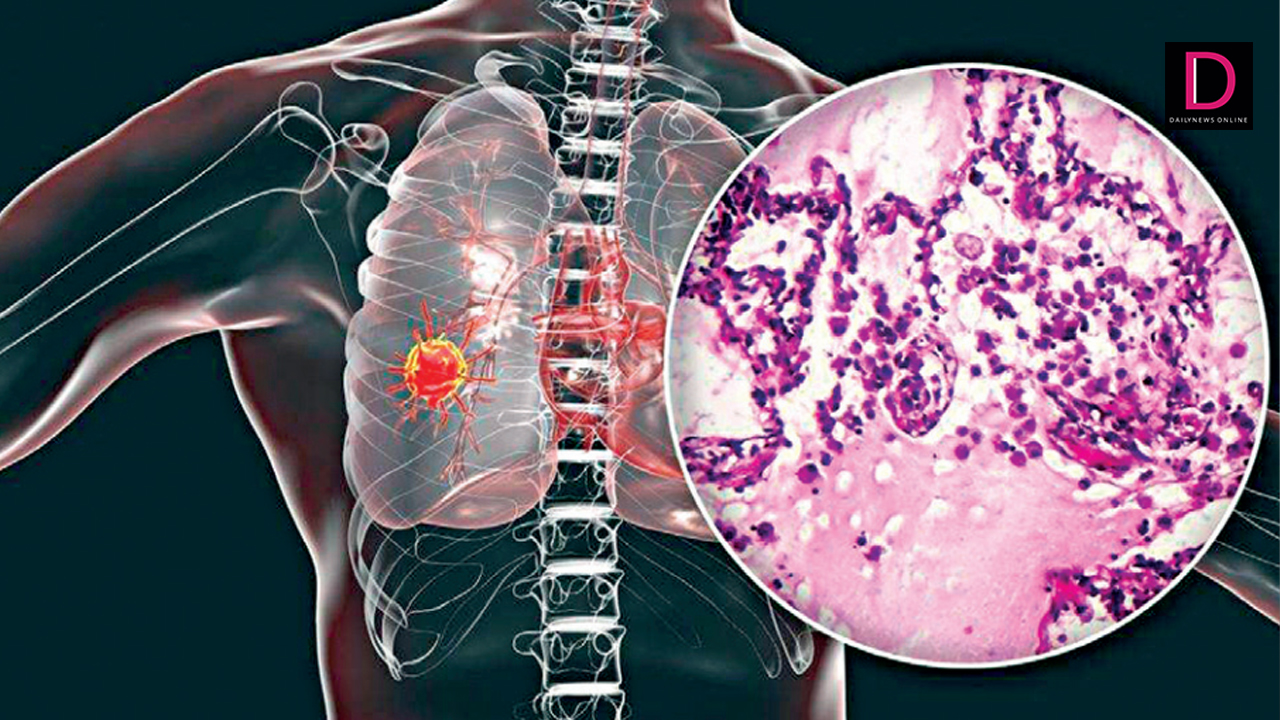

ทั้งนี้ เมื่อจำนวนมะเร็งที่เกี่ยวข้องกับการสูบบุหรี่ลดลง แต่สัดส่วนโดยรวมของมะเร็งปอดในผู้ที่ไม่สูบบุหรี่ รวมถึงมะเร็งที่เกิดจาก EGFR และการกลายพันธุ์ของยีนเฉพาะอื่น ๆ จะเพิ่มขึ้นโดยอาการที่พบบ่อยที่สุดของมะเร็งปอดไม่แตกต่างจากการป่วยด้วยสาเหตุอื่น คือจะมีอาการไอเรื้อรัง รวมถึงไอเป็นเลือด มีเสียงหวีดหรือหายใจถี่ มีอาการเจ็บหน้าอก เสียงแหบ น้ำหนักลดโดยไม่ทราบสาเหตุ เป็นต้น

อย่างไรก็ตาม ผู้ป่วยโรคมะเร็งปอดส่วนใหญ่ตรวจเจอเมื่อในระยะลุกลาม ทำให้การรักษาได้ไม่ดีมากนัก เนื่องจากตัวโรค มีการตอบสนองกับยาเคมีบำบัดได้ไม่ดี อย่างไรก็ตามจากการศึกษาล่าสุด จากสมาคมปอดนานาชาติ พบว่าอัตราการรอดชีวิตจากมะเร็งปอดดีขึ้น จากความก้าวหน้าในการตรวจวินิจฉัยและการรักษา โดยเฉพาะมะเร็งระยะที่ 4 มี ยาพุ่งเป้า (Target therapy) หรือ ยาภูมิคุ้มกันบำบัด (immunotherapy) แต่จะดีที่สุดหากตรวจพบเร็วรักษาเร็ว ยิ่งเพิ่มโอกาสในการรักษามีประสิทธิภาพมากขึ้น ดังนั้นหากรู้สึกว่ามีบางอย่างผิดปกติ ขอให้รีบปรึกษาแพทย์.